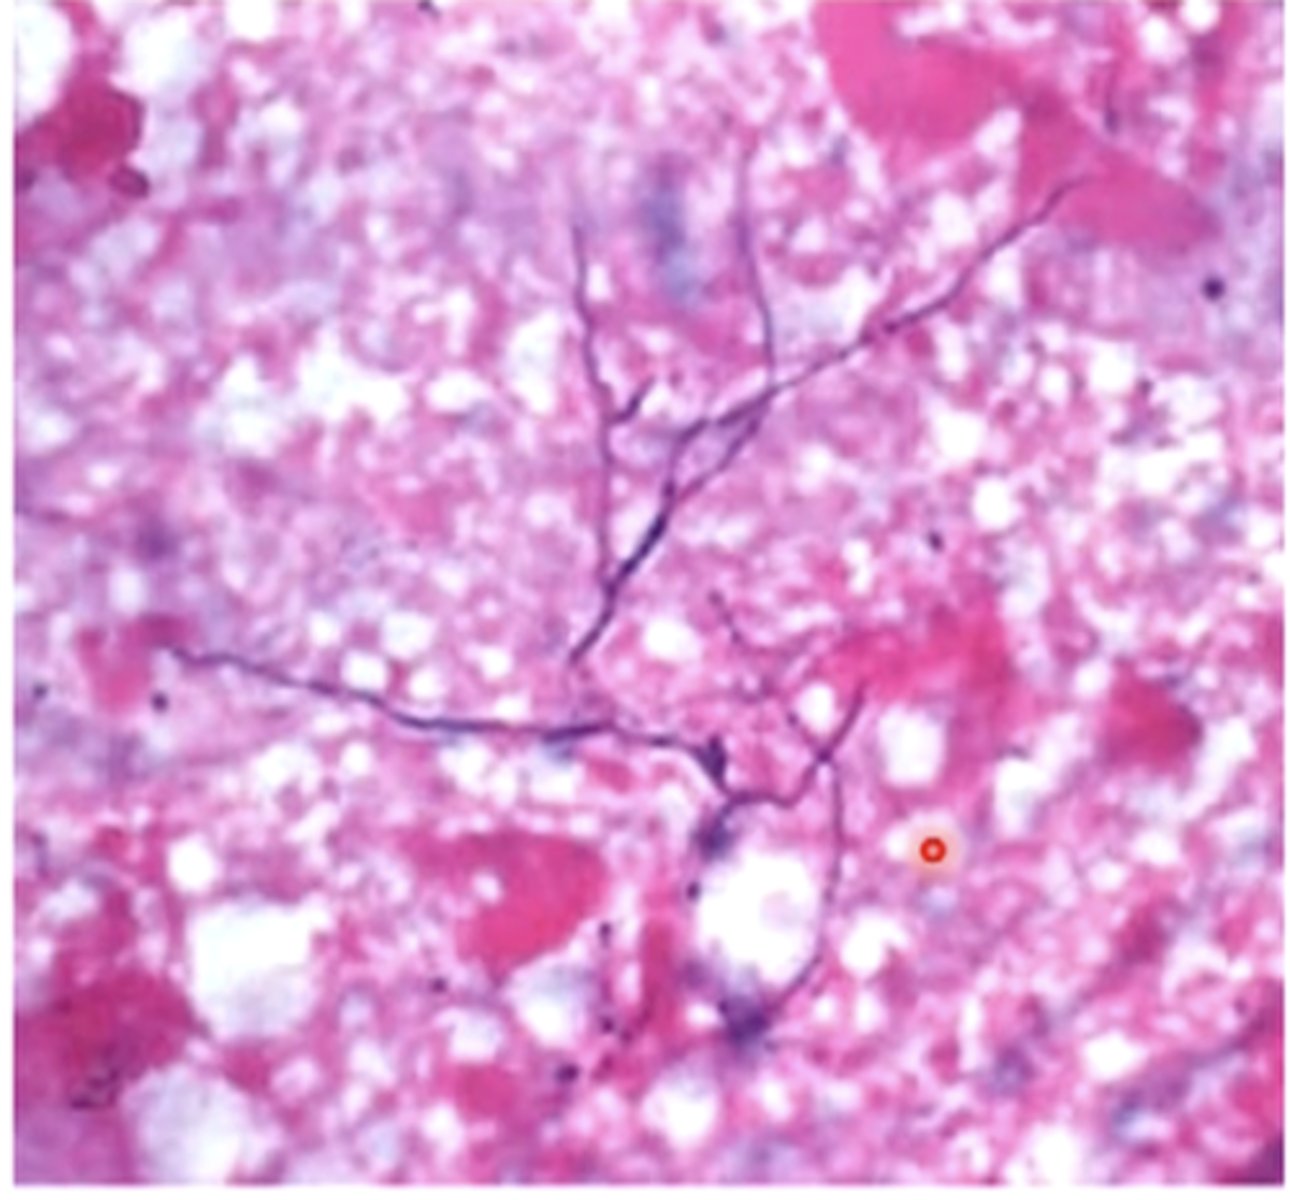

sulfur granules

fibrinous tracts of pyogranulomatous lesions from Actinomyces secrete purulent exudate that contains

bacterial filaments surrounded by club-shaped, mineralized calcium phosphate crystals

sulfur granules are made up of what

- exudates/aspirates may contain sulfur granules

sulfure granules from Actinoymces

- club shaped colonies with bacterial-sized filaments